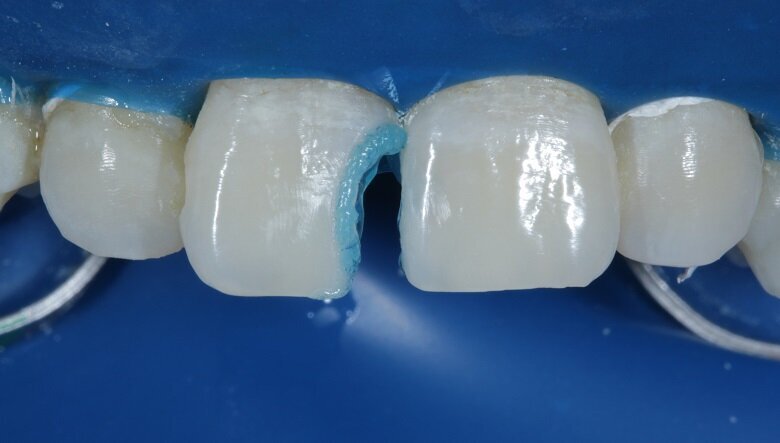

Total etch was done on both teeth with 37% phosphoric acid on the roughened surfaces for 30 seconds (Fig 10) and thoroughly washed with water. Bonding agent was applied and air dried for 20 seconds (Fig 11).

The tooth surface was then cured for 20 seconds. A free hand palatal shell was built using A2 enamel shade which gave the restoration a basic structure and is the first step of layering (Fig 12). Tooth no. 21 was built up palatally using A2 dentin and body shade.